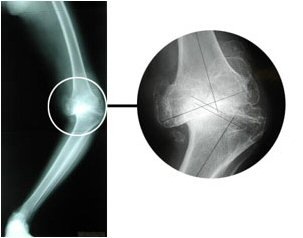

The lives of some elderly people are rendered miserable by progressive bow-leg deformity brought on by arthritic destruction of both knee joints.

Total knee replacement offers a chance for a return to a near normal life, but can be demanding on the surgeon when the condition has been allowed to progress to extremes.